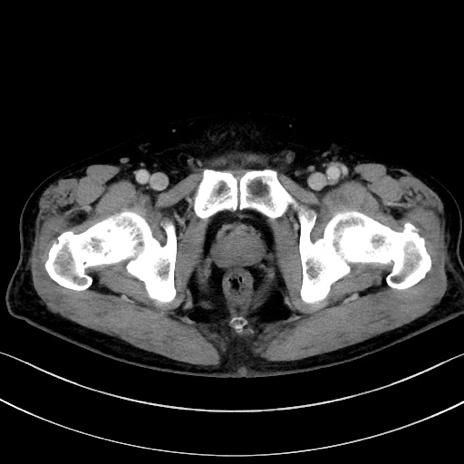

症例15(横断像)

【症例】70歳代男性

【主訴】腹痛

【現病歴】今朝から腹痛あり。全体的に痛い。特に左上の方。排ガスが今日はない。冷や汗が出る。

【既往歴】直腸癌術後

【身体所見】左側腹部〜上腹部に圧痛あり。腹膜刺激症状明らかなではない。軽度反跳痛。左下腹部に術後瘢痕あり。

【データ】WBC 7700、CRP 0.02